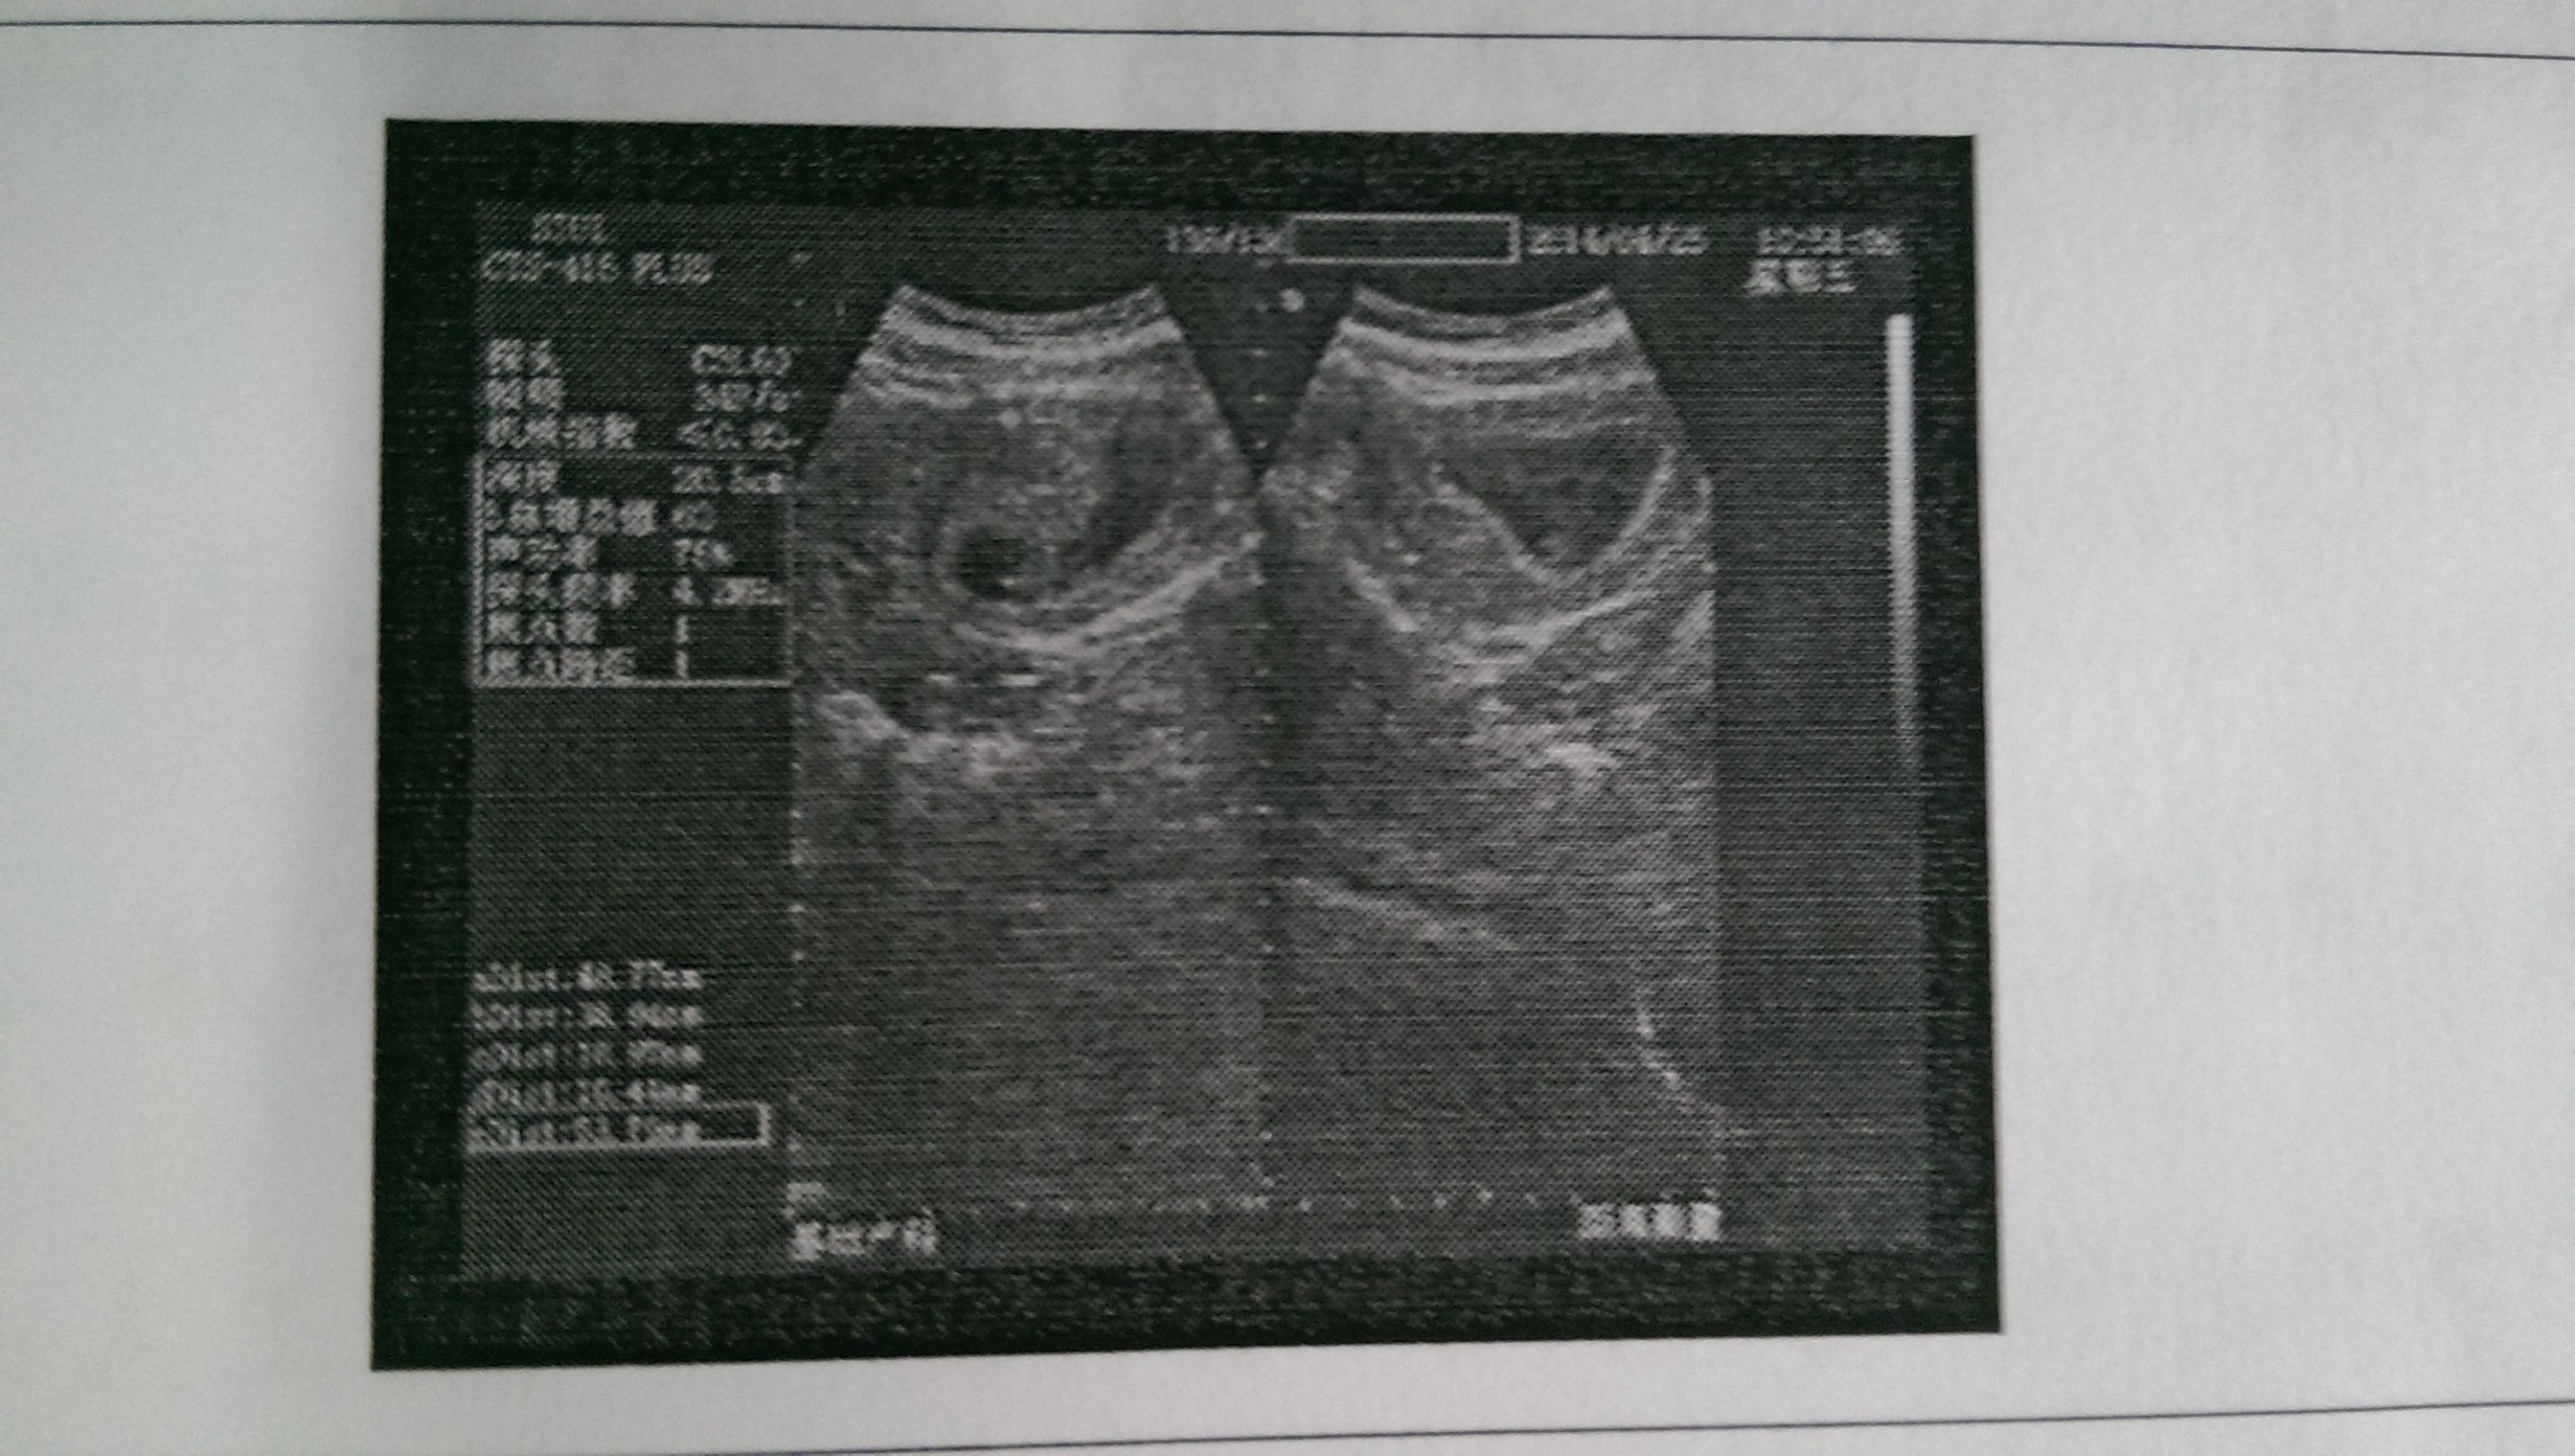

我是一个21岁的女生,最近怀孕了,去打了B超 当时看病的人多,医生也没告诉我胎儿多少天了 网上说 是从末次月经的第一天开始算,但是这样准确吗??我想问问医生我的胎儿有多少天了?要具体的。 点击展开 匿名用户 2014-04-26 06:04 为您推荐: 其他回答 病情分析: 怀孕时间是从末次月经算的。 指导意见: 每个人的胎儿发育可有差异,从B超上找不到你想知道的答案。 匿名用户 2014-04-26 06:17 相关问题 怀孕18周今天在医院做B超医生说胎儿头部才44说太小了我应该怎么办呢 我最后一次月经是4月21好,我怀孕几周啦但是我6月15号做b超医生说没胎心,没胚芽 怀孕36周加4天,今天检查说我宫口张开两公分,医生没有告诉我会不会早产!!!这是不是说我会早产呢!